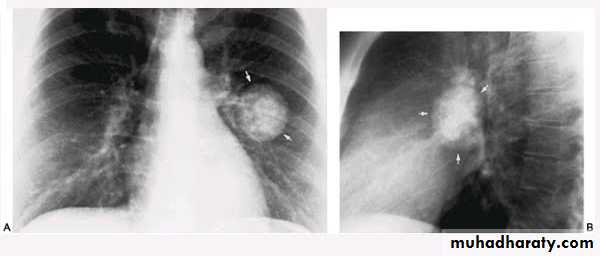

Nodular (coin) lesion in the left upper lung with irregular edge (most probably cancinoma